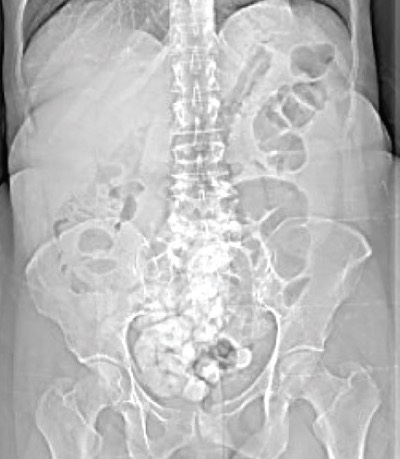

Bilateral Developmental Dysplasia of the Hip

A 12-year-old girl presented to with left-sided hip pain and a limp that had been progressively worsening over the past 8 months.